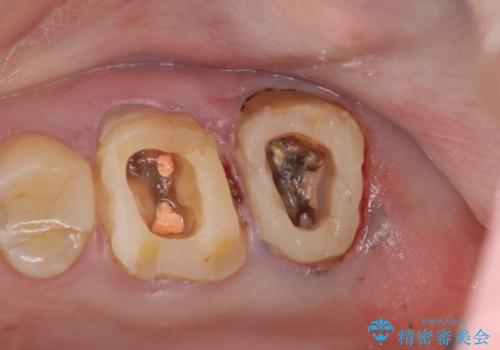

・咬合機能の回復 →セラミッククラウンの製作

深い虫歯・根尖性歯周炎・咬合機能の回復の問題を解決し良好な治療結果を得ることができました。